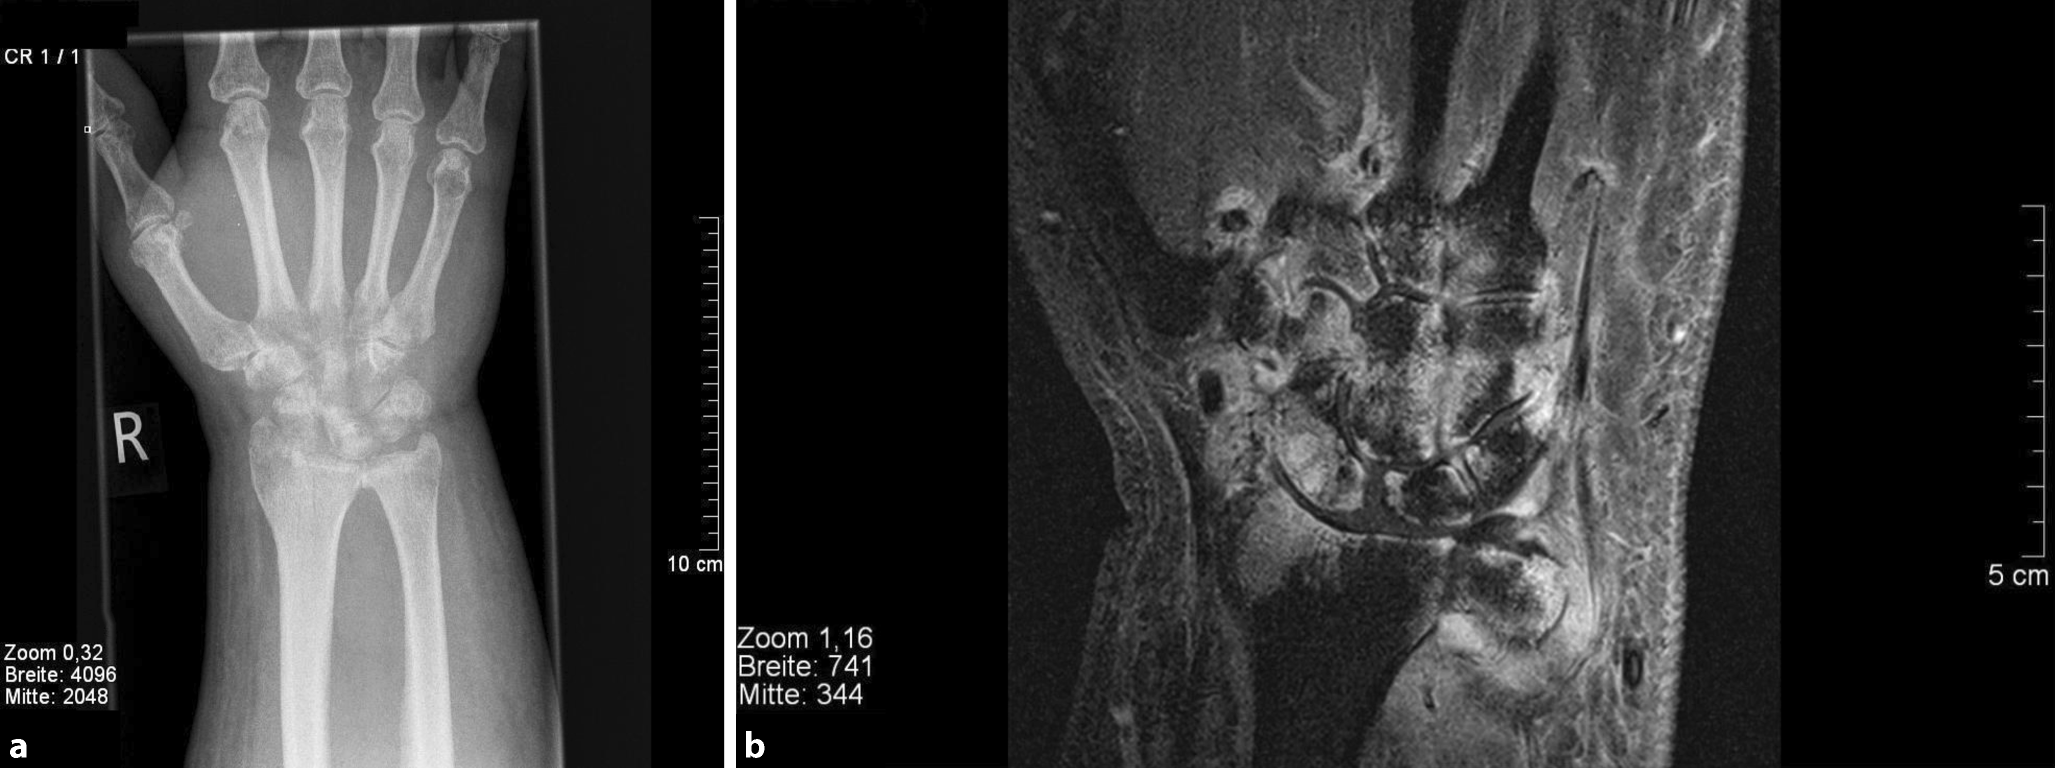

Bei der körperlichen Untersuchung fiel ein schmerzhaftes, gerötetes, überwärmtes und geschwollenes rechtes Handgelenk mit Ausbreitung der Schwellung über den Handrücken auf (Abb. 1). Die Bewegungsmaße im Handgelenk waren schmerzbedingt in Extension und Flexion eingeschränkt (nach Neutral-Null-Methode 20/0/20), der Faustschluss aller Finger inkomplett. Der Daumen war schmerzbedingt endgradig bewegungseingeschränkt. Der Patient war fieberfrei. Der Narbenbereich des einliegenden venösen Ports war klinisch unauffällig.

Abb. 1

Schwellung des rechten Handgelenks mit Ausbreitung über den Handrücken